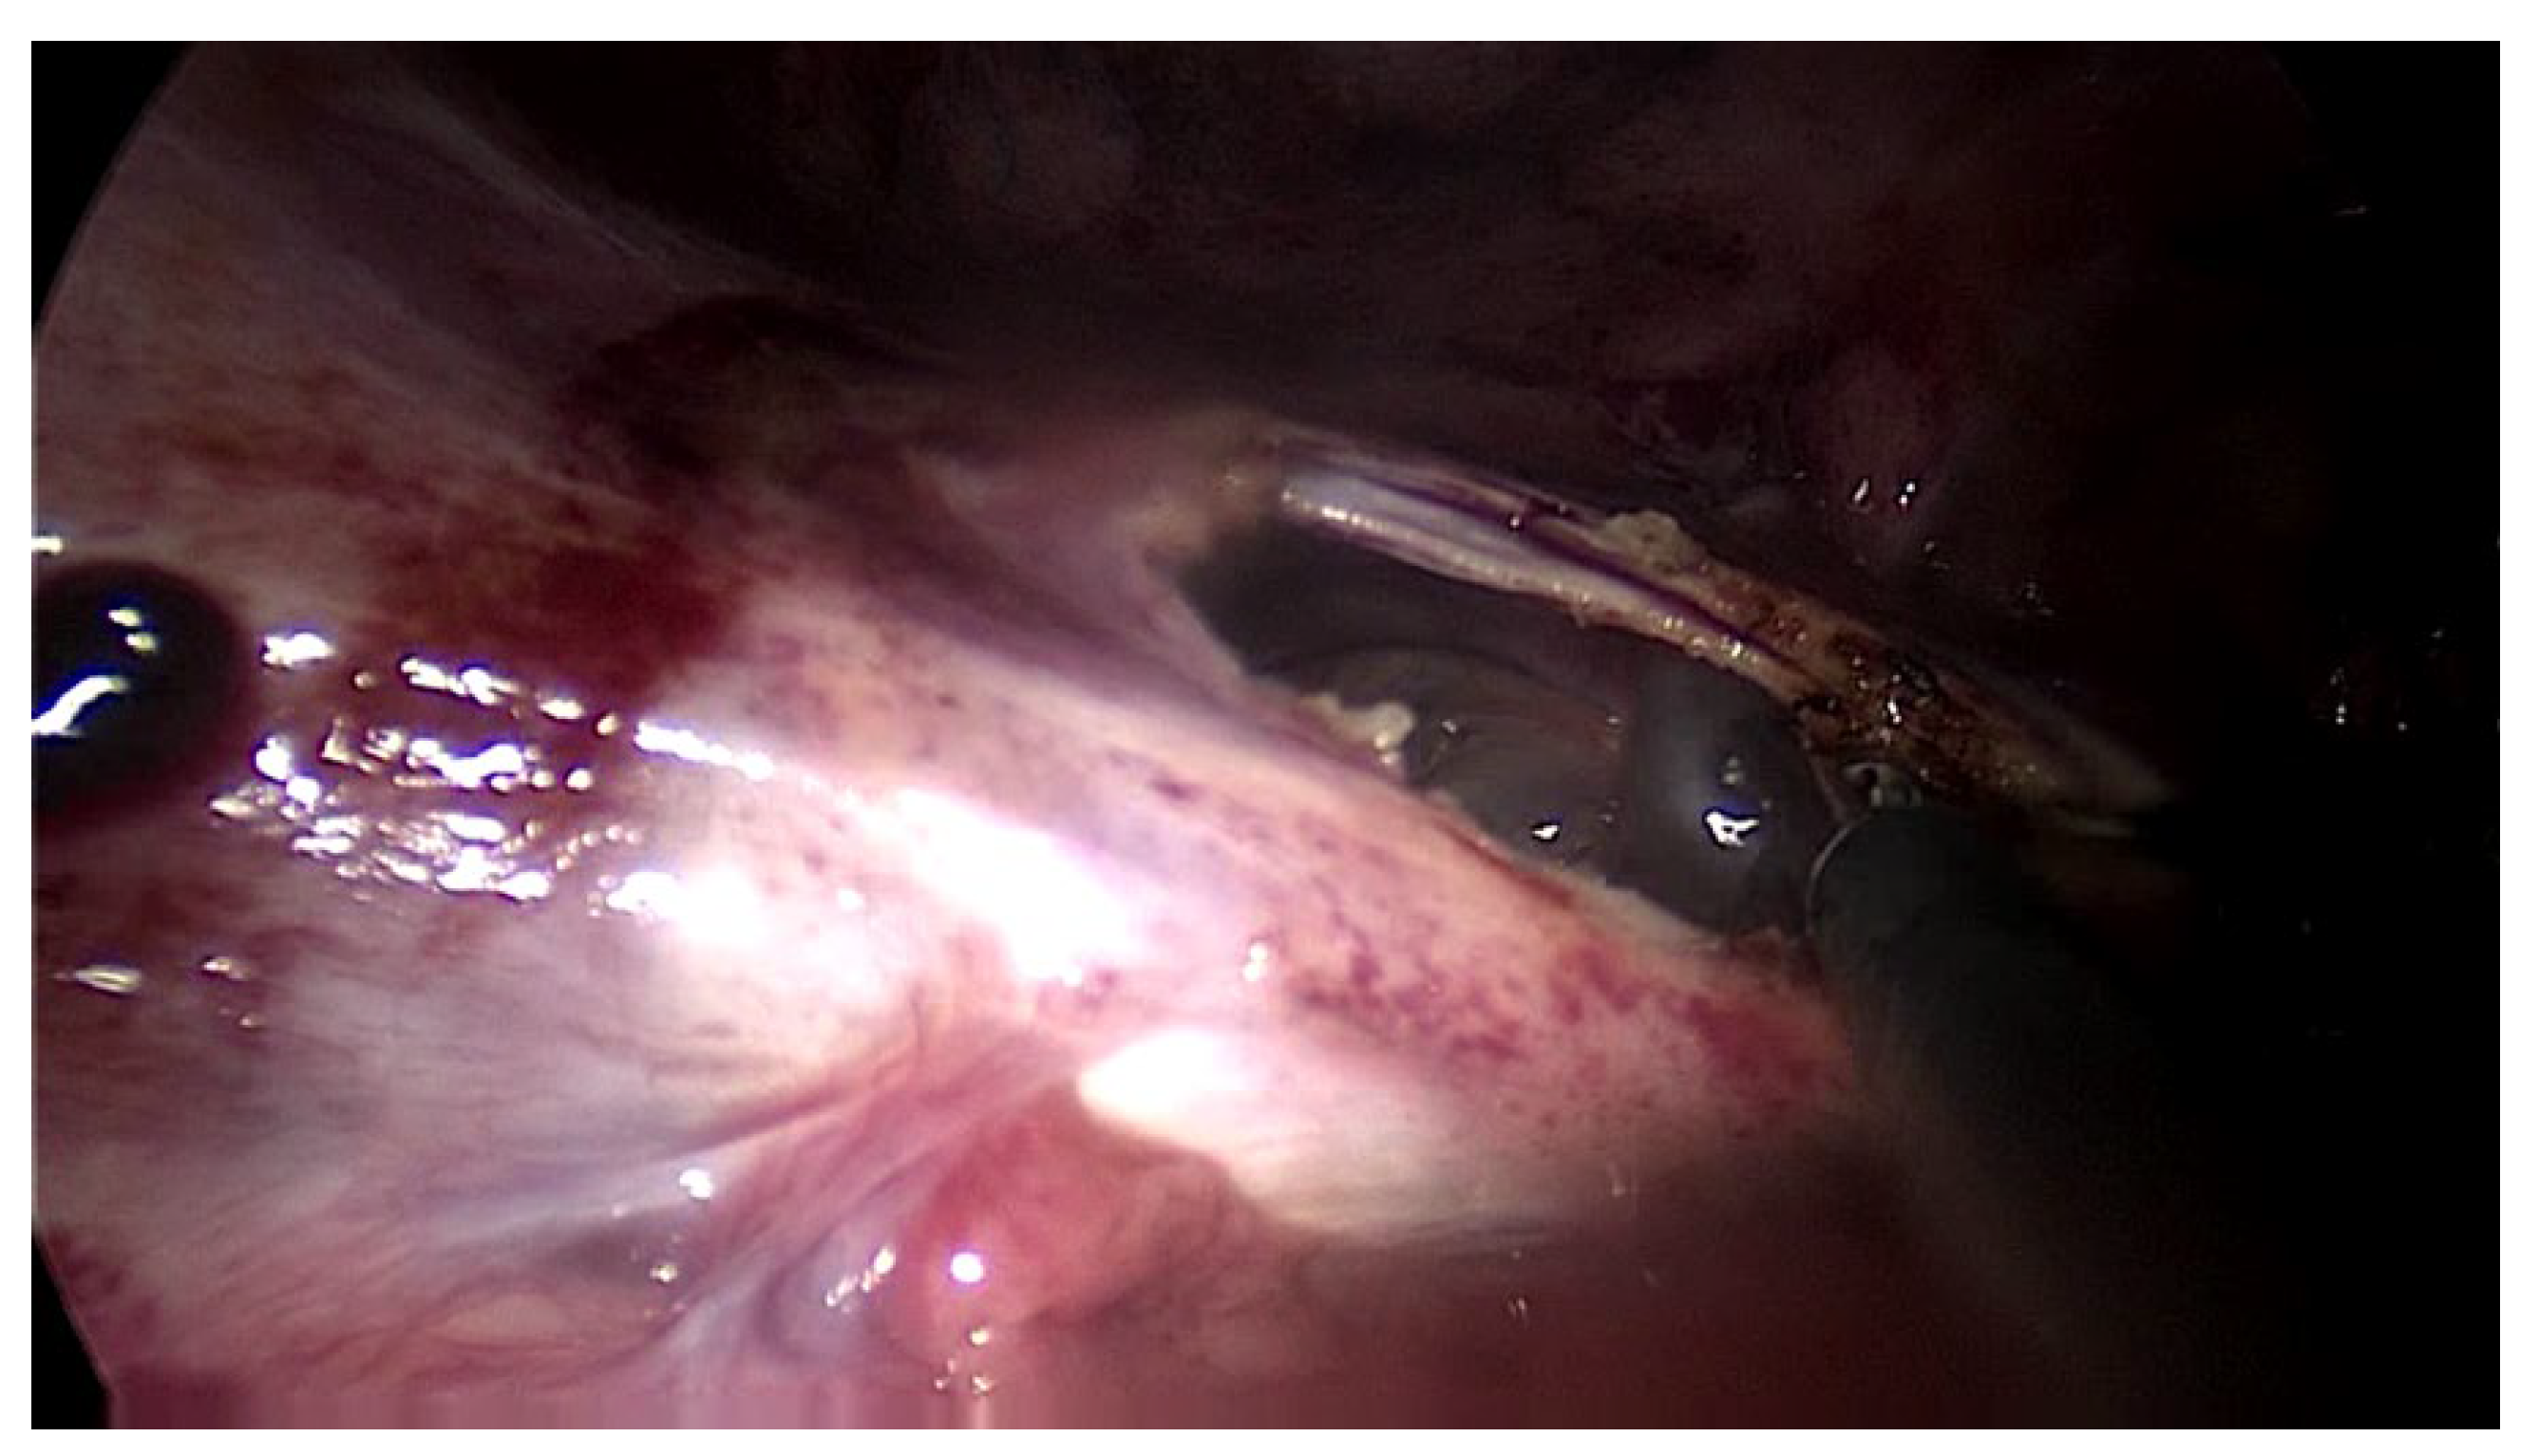

The second patient was a 44 year old woman who had undergone PD for 11 years. The patient was referred for nausea, vomiting and metrorrhagia accompanied by a palpable mass in the lower abdomen. A CT scan revealed the presence of an abdominopelvic tumor measuring 12 cm in diameter, suggestive of a uterine fibroid causing the compression of the rectum. A hemostatic curettage was performed in an attempt to postpone surgery, which proved unsuccessful. Then, laparotomy and a definitive transfer to hemodialysis treatment was decided. The intraoperative macroscopic appearance of the parietal and visceral peritoneum revealed only some areas of peritoneal fibrosis, except for the pelvic peritoneum, which showed extensive fibrosis (Figure 2). The fibromatous uterus was encapsulated in a pelvic “cocoon”, and the rectosigmoid junction adhered to this “pelvic block”.

The procedure then consisted of a total hysterectomy with bilateral adnexectomy. The adhesiolysis of the rectosigmoid junction from the pelvic block was performed with great difficulty, with the surgical procedure lasting 4.5 h. The patient had a slow postoperative recovery, as it was marked by a difficult resumption of the gastrointestinal transit.

Figure 2. Intraoperative finding: thickened peritoneum, ascites.

Jcm 13 02921 g002